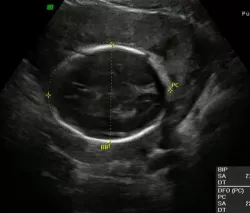

L’échographie du 1er trimestre

déterminer l’âge exact de la grossesse (en cas de discordance avec l’âge présumé de la grossesse :c’est généralement la date obtenue par l’échographie qui sera retenue)

déterminer le nombre de fœtus

rechercher une anomalie morphologique

effectuer le dépistage Trisomie 21.